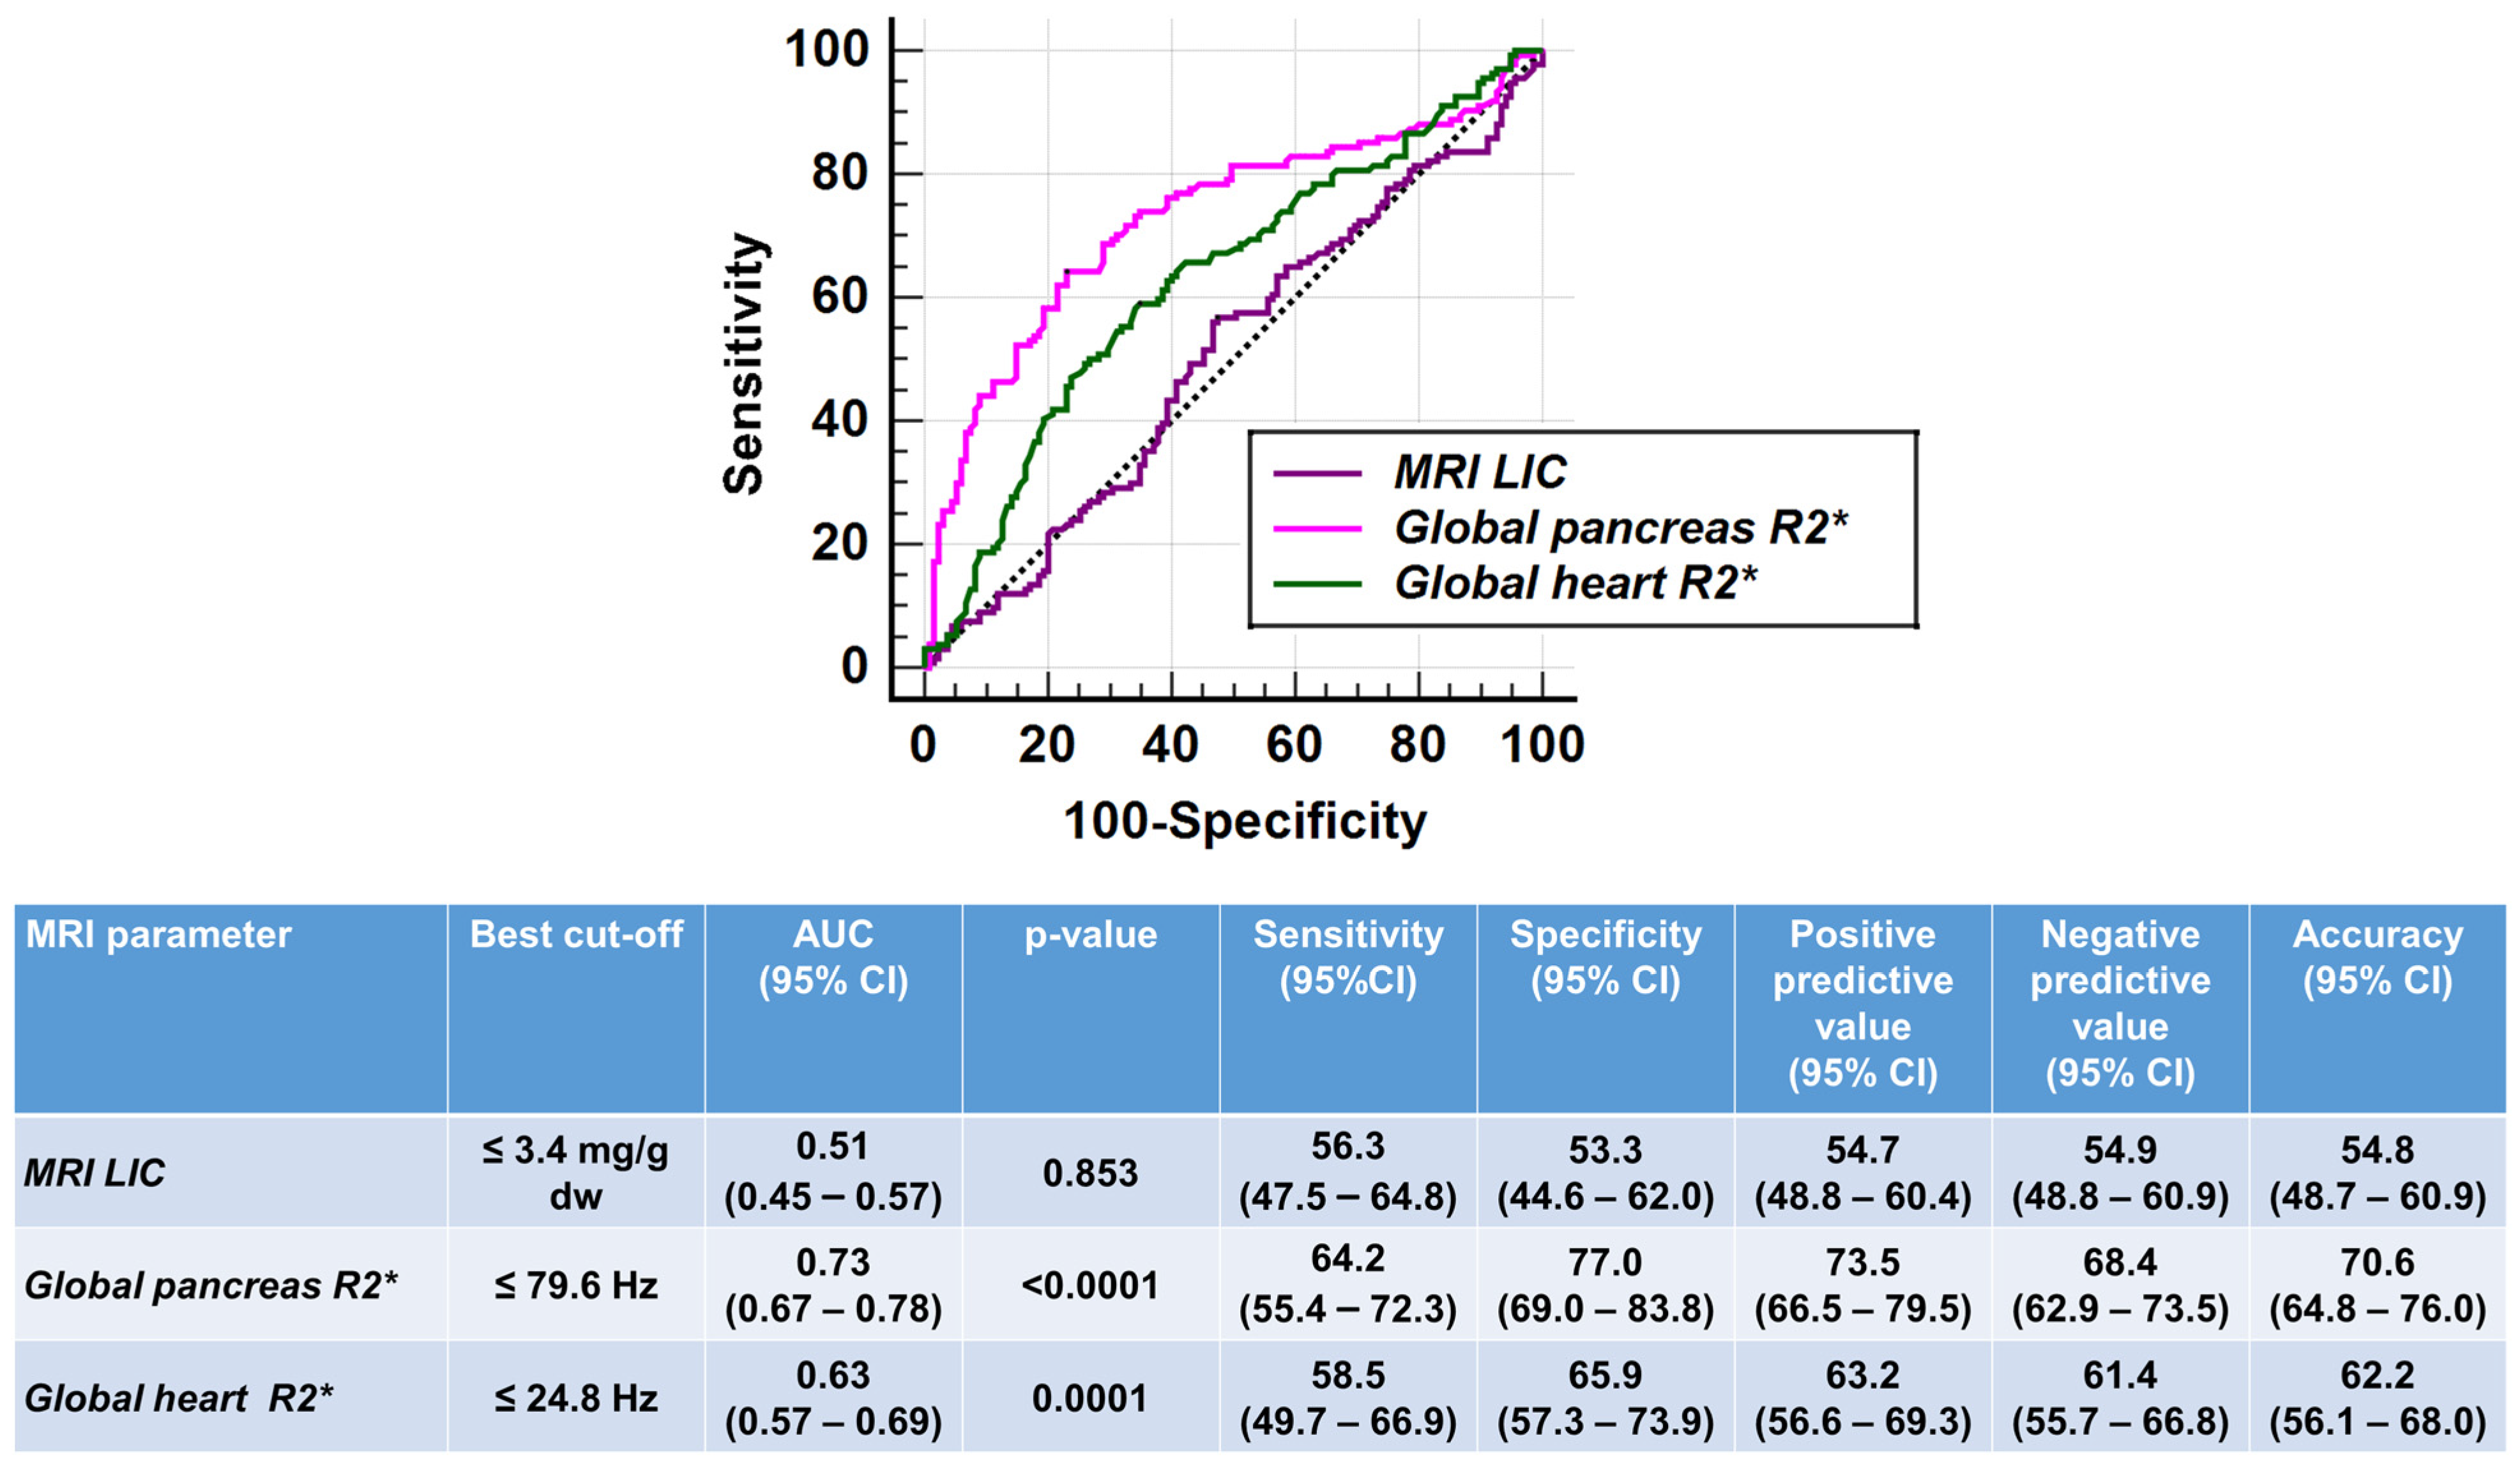

3.3. Comparison of Tissue Iron Levels between TI and TM Patients

| MRI LIC (mg/g dw) | 6.54 ± 14.68 | 5.22 ± 6.62 | 0.853 |

| Hepatic iron overload, n (%) | 87 (64.4) | 90 (66.7) | 0.701 |

| Global pancreas R2* (Hz) | 93.47 ± 93.23 | 148.38 ± 107.73 | <0.0001 |

| Pancreatic iron overload, n (%) | 92 (68.1) | 127 (94.1) | <0.0001 |

| Global heart R2* (Hz) | 26.19 ± 7.17 | 30.38 ± 16.57 | <0.0001 |

| Significant myocardial iron overload, n (%) | 4 (3.0) | 7 (5.2) | 0.540 |